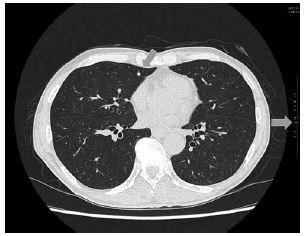

肺の結節は見逃さない

当院に導入されたSAI viewer にはAIを用いたいくつかの診断支援ツールが搭載されているが、その中でもっともよく使うのは肺結節検出のCAD(コンピュータ支援診断)である。ショートカットキーを押して数秒で、肺全体をスクリーニングして結節を検出し、チェックをいれてくれる(図2)。実際には肺野をじっくりみてから、確認のためにCADを走らせる事が多い。感度が高いので必要以上に拾ってしまうのだが、横のバーでは結節のサイズに合わせて矢印も大きくなるので、ある程度取捨選択ができる。少なくともこれで初期の肺転移を見逃す事はないだろう。日常診療における見落とし防止と、読影の負荷軽減に大いに役立っている。